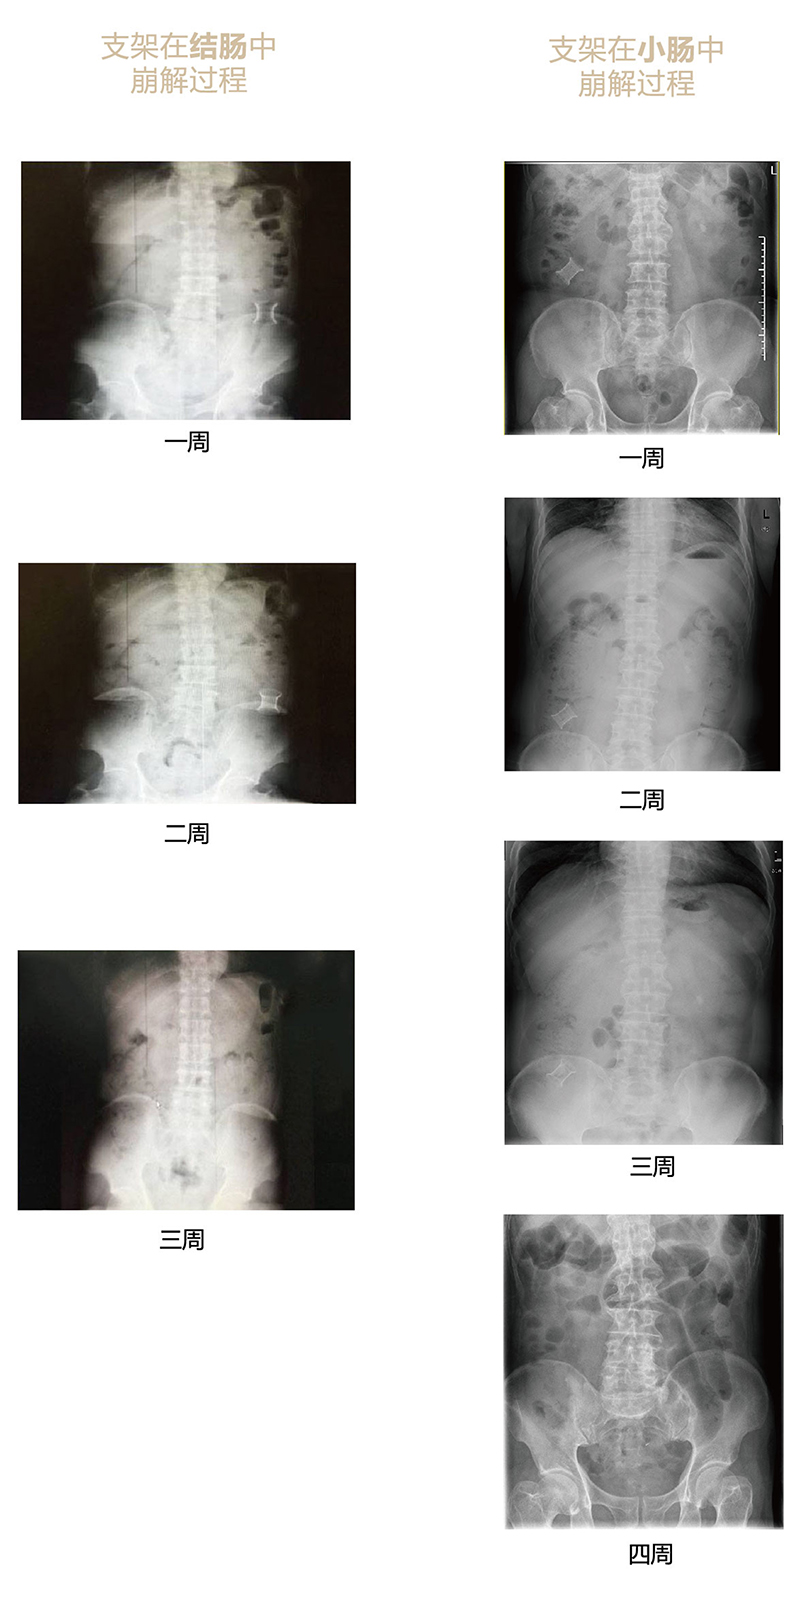

“可崩解腸道吻合器”由聚乙醇酸(PGA)與硫酸鋇按重量比7:1混合注塑制成,在X線下顯影,可動(dòng)態(tài)追蹤可崩解腸道吻合器(支架)在腸道內(nèi)崩解過程。

為解決該問題,蔡秀軍教授在“支架法空腔臟器吻合技術(shù)”的理念基礎(chǔ)上,又發(fā)明了“蔡氏腸轉(zhuǎn)流術(shù)”,這是一種應(yīng)用“可崩解腸道吻合器HB型(可崩解腸轉(zhuǎn)流支架)”(發(fā)明專利號:201910794214.3),的支架法腸道轉(zhuǎn)流術(shù),此創(chuàng)新術(shù)式既能保護(hù)低位吻合口,更避免了回納術(shù)??杀澜饽c轉(zhuǎn)流支架在直腸癌根治術(shù)中植入遠(yuǎn)端回腸,可確保完全阻斷腸腔,用腸造瘺管在轉(zhuǎn)流支架近端行腸造瘺,起到完全轉(zhuǎn)流的作用。腸轉(zhuǎn)流支架在二至三周內(nèi)逐漸崩解,并在四周內(nèi)完全排出體外,恢復(fù)腸道通暢后拔除造瘺管,避免了傳統(tǒng)造口回納的二次手術(shù)。該創(chuàng)新術(shù)式具有方法簡單、吻合時(shí)間短、人體內(nèi)無異物永久殘留、不破壞吻合口粘膜下血管,并能預(yù)防吻合口漏、可避免人工肛門留置及二次手術(shù)、治療周期可縮短至二至四周、患者生理心理創(chuàng)傷顯著減少。